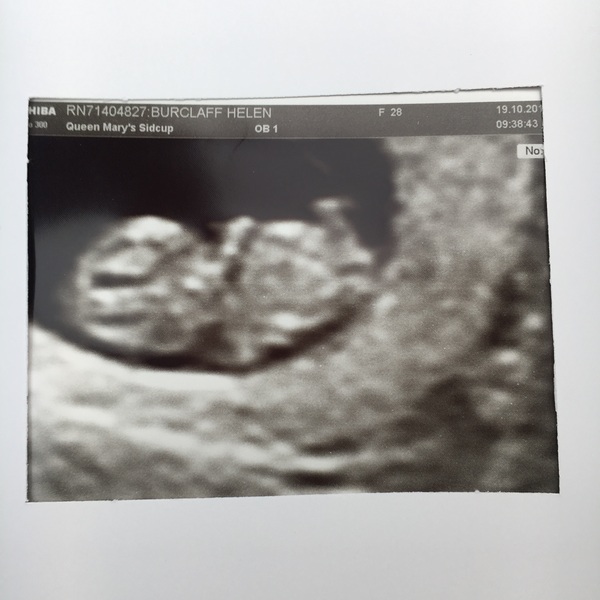

So... all seems ok... wriggly little raspberry at 8+5 Smile

raspberry lovely scan pic! Glad to hear everything is going well

Brilliant news raspberry and lovely pic! I had my scan a week before you and it's amazing to see how much they change in that time!